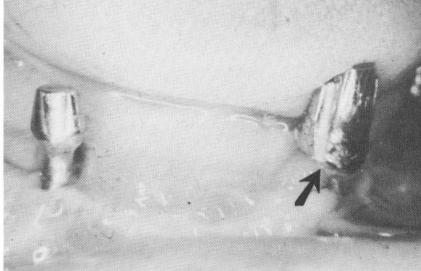

An accurate measurement of the soft tissue over-lying the four areas where the abutment posts will protrude should also be taken and sent to the technician. In this manner the height of the necks can be accurately determined. The tissue in the mandible is usually no thicker than 1 to 2 mm. However, if the tissue is not measured accurately and the neck is too long, the prosthesis-bearing post may be made much too short to firmly hold the superstructure. As an example, in one case it was necessary to cast a gold coping to cover the extra long neck so that the foreshortened abutment post could gain retention (Fig. 12-19). Unnecessarily long necks may also cause tension that results in the exposure of the primary strut (Fig. 12-20) . Such a situation may be

Fig. 12-19. An extended gold coping is sometimes cemented over an improperly designed implant post. In this case too much of the narrow neck below the post was exposed; the neck was made too long at the expense of the fore-shortened post, greatly reducing its retentive qualities. The gold coping restores the anatomy, improving the retention required to hold the implant denture. Note also the excessively long neck and short post on the right side, which was also improperly designed.

1 Extended gold coping cemented on poorly designed dental implant post